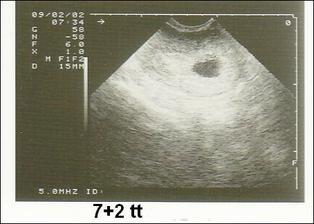

so.19.9.2009 40tt narodil se nám chlapeček Honzík v 11:25 hod. vážil 3900 g a měřil 53 cm